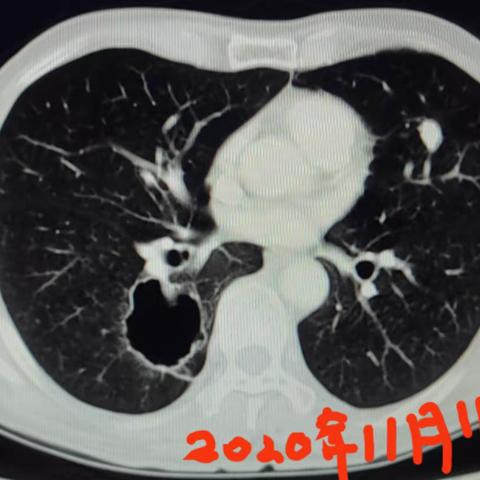

一例肺部空腔合并感染病例分享